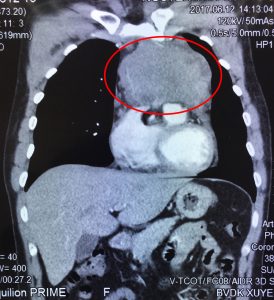

BVXA – BỆNH HIẾM: RÒ MẠCH TỤY SANG TĨNH MẠCH, ĐIỀU TRỊ THÀNH CÔNG BẰNG CAN THIỆP MẠCH MÁU DƯỚI DSA.

Ngày 08/6/2017, các bác sĩ hai chuyên khoa Ngoại Tổng Quát và Trung tâm Can thiệp Tim Mạch tại BVXA đã phối hợp can thiệp điều trị thành công cho bệnh nhân V.T.T. (sinh năm 1962, ngụ tại Huyện Hòa Thành, Tỉnh Tây Ninh) bị dò động mạch tụy lưng vào tĩnh mạch cửa. Đây […]